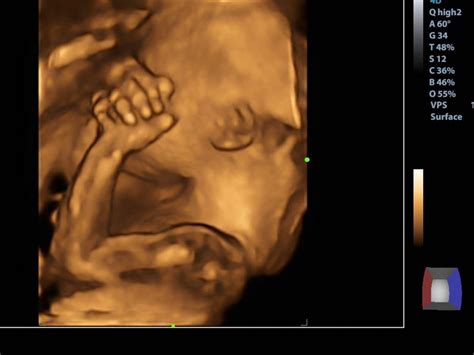

Podrobný prehľad ultrazvukových vĺn: ich vlastnosti, charakteristiky šírenia, výkonu, absorpcie a kavitácie. Vysvetlenie základných princípov a aplikácií v priemysle a medicíne.… Zobraziť viac